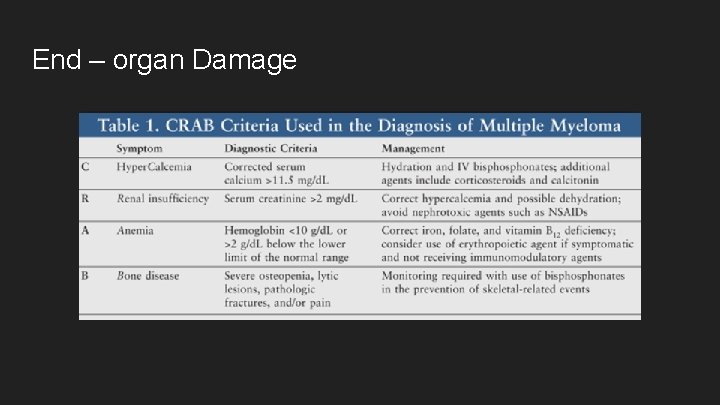

End – organ Damage